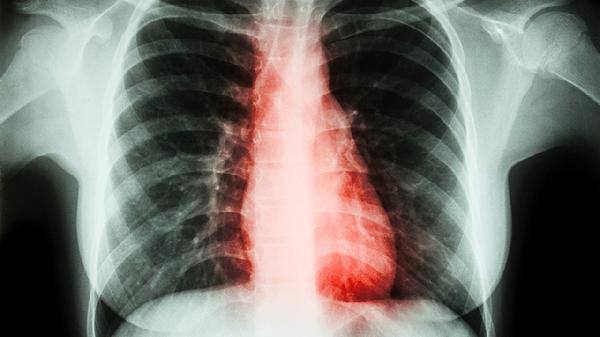

肺结节可通过活血化瘀、软坚散结类中成药调理,常用药物包括桂枝茯苓丸、小金丸、夏枯草胶囊等。肺结节的形成多与气滞血瘀、痰湿凝聚有关,治疗需结合辨证分型。

肺结节患者日常应保持情绪舒畅,避免忧思气结。饮食宜清淡,多食海带、薏苡仁等化痰散结食材,少食辛辣刺激之物。适度练习八段锦、太极拳等导引术促进气血流通,定期复查胸部CT观察结节变化。若结节增长迅速或出现咯血等症状,应立即就医排除恶性病变。